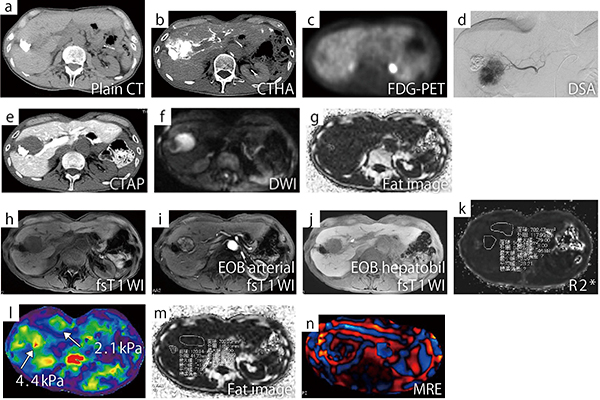

図2に示す症例は12年前にTACEを施行した患者で,新たに肝細胞癌を発症し,血管造影では多血化が認められた(図2 d)。造影CTでは門脈相で低吸収となり,門脈の関与がないことがわかる(図2 e)。拡散強調画像では強い拡散制限を受けており,細胞密度がきわめて高い腫瘍であることがわかる(図2 f)。Fat imageでは,リピオドール残存部が高信号を示している(図2 g)。

脂肪抑制T1強調画像は静脈相で強い濃染を示し(図2 i),肝細胞相は低信号を示した(図2 j)。

MRE(図2 l)では,腫瘍の部分が4.4kPa,背景肝は2.1kPaであった。結局,悪性リンパ腫と診断されたが,多角的な情報を得ることで,診断に生かすことができた例である。

図2 悪性リンパ腫(70歳代,男性)

HBs抗体(陽性),HBe抗体(陽性),HBc抗体(陽性),PIVKAII↑。12年前にHCCに対しTACEを施行。